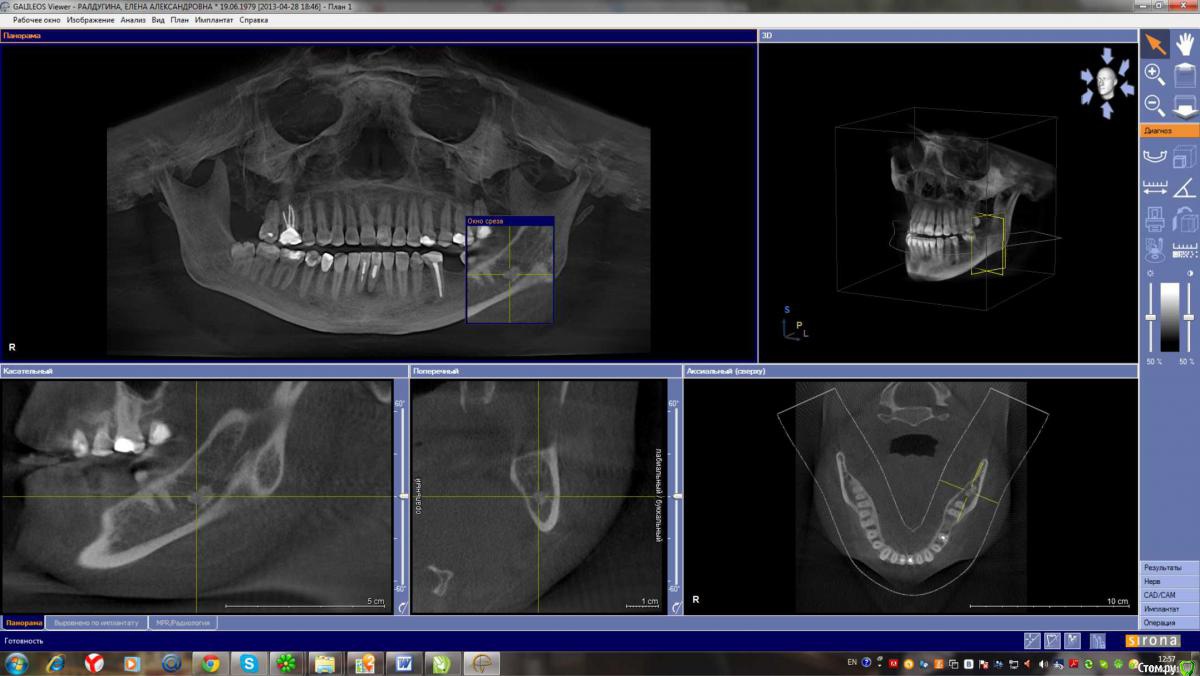

Лена35 Опубликовано 1 февраля, 2015 Автор Поделиться Опубликовано 1 февраля, 2015 кт апрель 2013кт ноябрь 2013последнее кт 2014Удаление сложное было? Не могу прицелиться, чтобы верхний корень было хорошо видно, но он там - в клинике с докторами мы смотрели его, он прямо в десну упирается и жжет там, но не воспаляется, не опухает, не гноится. Может потому что я на нвпс периодически сижу. Или дело вообще не в этих штуках? А как сказали артролог и невролог = миофасцеальный болевой синдром, триггерные точки, повреждение связок при вправлении вывиха... Но почему боль чаще сего я чувствую в области этого верхнего корня? И как долго еще это все будет болеть? Буду благодарна вашим обнадеживающим ответам. Заранее спасибо. Именно от боли острой в этой зоне я мучаюсь после вывиха более четырех месяцев. А до этого в этой зоне я чувствовала периодически , как будто зуб растет и думала, что фантомные боли, я только в сентябре узнала, что эти штуки у меня там есть. Операцию делать не хочу, боюсь осложнений. Но если боль от этого, то жить так тоже не хочу. И как делать операцию, если у меня открытие рта 2,5 см? Ссылка на комментарий

Alejandro Опубликовано 1 февраля, 2015 Поделиться Опубликовано 1 февраля, 2015 Я бы начал с удаления 27-го зуба, далее необходимо разобраться с лимфаденитом (если он ещё будет в стадии обострения). Образование в области нижнечелюстного канала очень похоже на один из корней 38 зуба, я бы предложил его удалить. А открывание рта как давно ограничено? Ссылка на комментарий

Alejandro Опубликовано 2 февраля, 2015 Поделиться Опубликовано 2 февраля, 2015 как Вы по КТ увидели лимфоденит? Выдернуть 27 мне еще никто не предлагал. Поначалу зубы лечатся вроде как эндодонтически.... Про лимфаденит Вы в 26 посте сами сообщили. Сделайте скрин среза в области 27-го, там не очень всё хорошо на верхушках корней. И, кстати, случаи когда зубы приходится удалять без эндодонтии не так уж и редки, к сожалению... Ссылка на комментарий